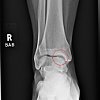

An X-ray showed a lesion on my talus bone. (Another angle even showed a little piece of cartilage that had broken off.) The doc seemed to think that was causing my click, and sent me for an MRI. That was in October. I didn’t see any real point in undergoing surgery to repair an ankle that wasn’t misbehaving, and besides, it was my foot that was hurting.

I got one that day. He took a peek at it, and told me I’d blown a hole in my bone that was 10 mm across (about a third of the width of the whole thing).